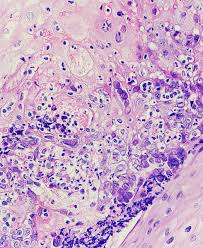

Pathology Outlines Herpes Simplex Esophagitis

Pathology Outlines Herpes Simplex Esophagitis from www.pathologyoutlines.com